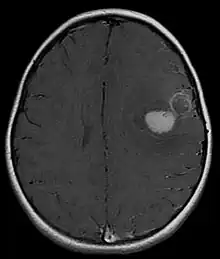

Magnetic resonance image of PNET

Most children that develop primitive neuroectodermal tumors are diagnosed early in life, usually at around 3–6.8 years of age.[2] Symptoms patients present at time of diagnosis include irritable mood, visual difficulties, lethargy, and ataxia.[2] The circumference of the patient's head might also become enlarged and they might be subject to seizures, especially if they have less than one year of life.[2]

Several analysis can be used to determine the presence of the disease. Physical examinations showing papilledema, visual field defects, cranial nerves palsy, dysphasia, and focal neurological deficits are evidences for possible tumor.[2] PNETs can also be spotted through computed tomography (CT) and magnetic resonance imaging (MRI).[2] In images produced by MRIs, an irregular augmentation among a solid mass will indicated the presence of tumor.[3] However, the results of MRIs are usually ambiguous in defining the presence for this specific tumor.[2] In CT scans, the presence of PNETs will be indicated by an elevated density and an increase in volume of the brain.[2] The CT scan can also show calcification,[3] which is present in 41-44% of PNET cases.[2] Since the tumor can be replicated in other parts of the nervous system through the cerebrospinal fluid (CSF), a CSF analysis can also be conducted.[2] A spinal MRI is a fourth type of analysis that is useful in investigating the level of tumor propagation to the spinal cord.[2]